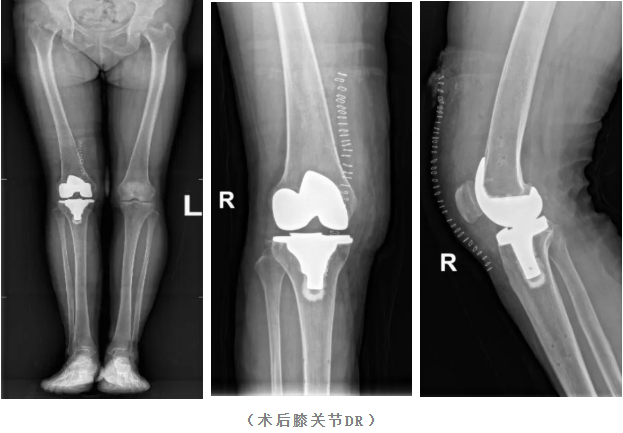

手术中,机器人的机械臂在导航系统实时引导下进行截骨操作,将误差严格控制在0.5毫米与0.5度以内。这种远超人手稳定性的精度,确保了假体植入位置与术前规划毫厘不差,为实现最佳下肢力线和关节平衡奠定了坚实基础。

3.微创化与软组织保护

传统手术为定位常需进行股骨开髓,这会导致额外失血和创伤。机器人辅助系统采用无髓腔定位技术,避免了这一损伤。同时,系统能根据术中软组织张力实时反馈,帮助医生以最小化的软组织松解实现完美的关节间隙平衡,从而将手术创伤降至更低,出血量较传统手术减少20%以上。

在机器人“最佳助手”的辅助下,手术流程流畅顺利,整体出血量极少。得益于手术的精准与微创,患者术后恢复迅速。

·术后次日,孔大妈即可在医护人员指导下站立并开始行走。

·术后短期,膝关节疼痛得到显著缓解,关节活动度良好,对手术治疗效果感到非常满意。